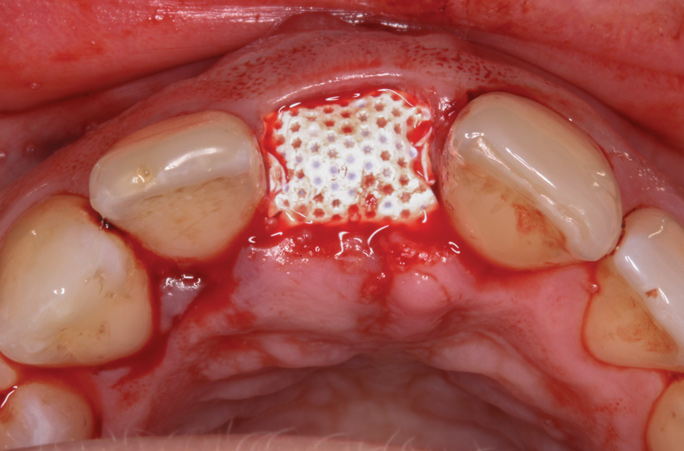

A d-PTFE (Cytoplast) barrier was trimmed into the shape of an ice cream cone to conform to the socket's morphology (Figure 4). The barrier was placed inside the alveolus and compressed laterally into the buccal dehiscence (Figure 5). Small-particle, mineralized cancellous freeze-dried bone allograft (ie, 0.25 mm to 1 mm) was inserted into the socket and packed against the barrier. The socket was filled 1 mm to 2 mm above the alveolar crest to aid in attaining a convex rather than concave gingival architecture at the socket opening upon removal of the barrier. The barrier was tucked under the palatal flap (3 mm) and secured with Vicryl 4-0 single interrupted sutures (Figure 6 through Figure 8).

Fig 6. Small-particle allograft was placed in the socket.

Figure 6

Fig 7. The d-PTFE barrier was tucked under the palatal flap (3 mm).

Figure 7